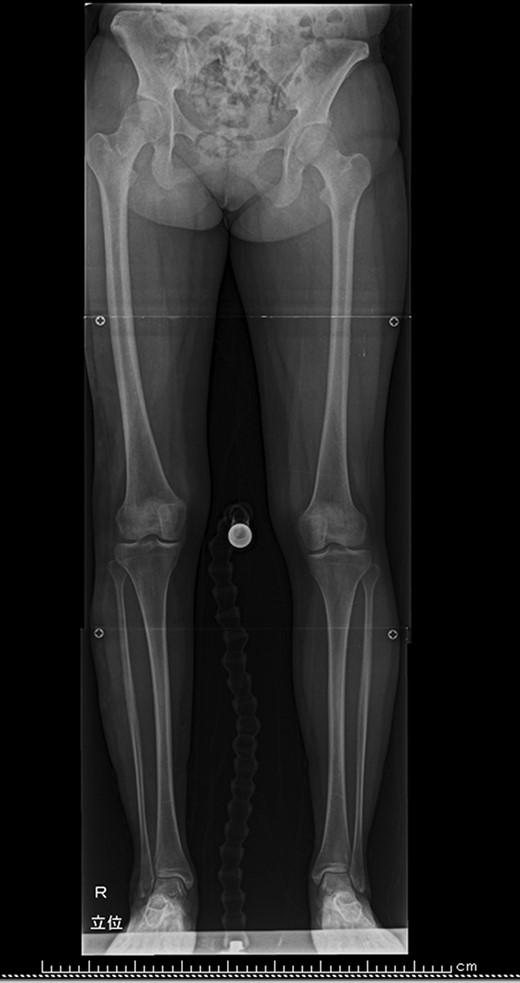

To rule out polyostotic type fibrous dysplasia, further questioning was done. Although she had not realized by herself, physical examination revealed that her right leg was longer than the other (Fig. 3a). Difference in circumferences was not obvious. Subcutaneous venous dilatation on the lateral side of her right leg was observed (Fig. 3b). Standing radiograph of the lower extremities showed leg length discrepancy of 31 mm (Fig. 4). In MRI venography (Fig. 5), vein with large caliber running from right lateral lower leg to great saphenous vein was observed. Venous density in the right leg was higher than the other, suggesting existence of venous malformation. The condition was diagnosed as Klippel–Trenaunay syndrome.

Standing radiograph of the lower extremities. Leg length discrepancy was 31 mm. Tibial length discrepancy was 21 mm.